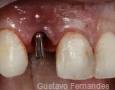

Immediate Implant Placement

Summary Case - By Gustavo Fernandes

Pictures

Surgery